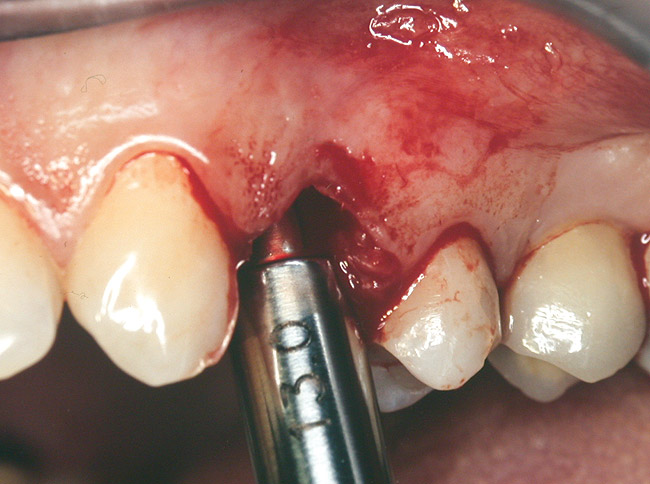

At the time of surgery, local infiltrative anesthesia was administered (lidocaine 2% with epinephrine, 1:100,000). A full-thickness mucoperiosteal flap was raised. The initial osteotomy was performed on midcrestal bone using a rose-headed bur. To prepare the osteotomy site for implant placement, sequential alternating osteotomes with variable conicity were used, drilling 2-mm shorter than the length of the implant to be placed (Figure 3A and Figure 3B). The implants presented initial primary stability (Figure 4), the cover screws were placed, and the implants were submerged for a healing period. The tissue was approximated, and the patient was instructed not to wear any denture or to place pressure on the healing site.

Figure 3A and Figure 3B Alternating osteotomes with variable conicity used to perform the alveolar remodeling in the area of tooth No. 24.

Figure 3a  Alternating osteotomes with variable conicity used to perform the alveolar remodeling in the area of tooth No. 24.

Figure 3a

Figure 3b  Alternating osteotomes with variable conicity used to perform the alveolar remodeling in the area of tooth No. 24.

Figure 3b